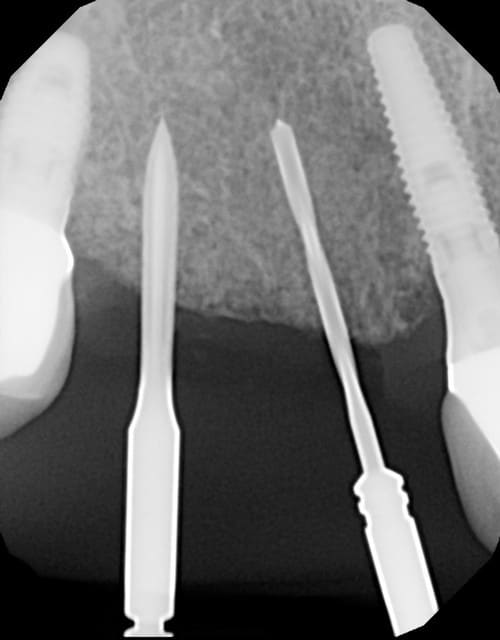

Espace de 20 mm

Mais angulation des implants déjà posés ne permet pas de placer plus de 2 implants

On voit bien l'angulation des implants déjà posés et des forêts initiaux.